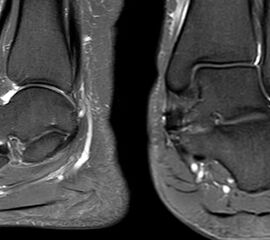

Die Abbildungen 4.2.a bis d zeigen den typischen Aspekt einer talacalcanearen Coalitio. Es besteht nur eine linksseitige, symptomatische Coalitio talocalcaneare (4.2.a und c); das 35 Tage zuvor angefertigte MRT zeigt keine auffälligen Signalveränderungen (4.2.b und d).